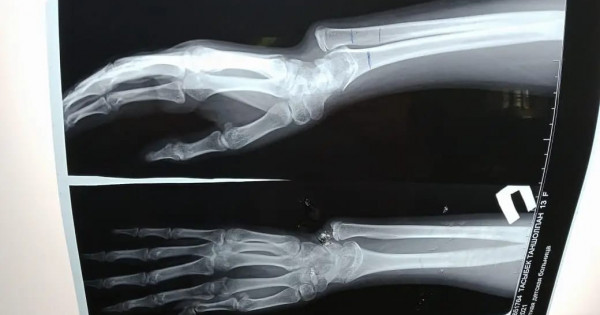

Науқас осыдан бірнеше жыл бұрын қолын ауыр жарақаттап, шынтақ сүйегі өсіп, кәрі (лучевая) сүйегі өспей қалған. Салдарынан қолындағы сүйектері қисайып, өздігінен қимыл жасауға кедергі келтірген.

«Ота жасалған науқас үш ай бұрын қалалық клиникалық балалар ауруханасына кеңес алуға келген болатын. Тексере келе науқаста жарақаттың салдарынан сүйегі қисайғаны анықталды. Операцияны бірден жасамадық. Себебі мұндай ота баланың сүйек өсуі тоқтауға жақындаған кезде жасалады. Операция кезінде қатты өсіп кеткен сүйекті қысқартып, өспей қалған сүйекке жалғап, арнайы құрылғымен бекітіп бердік. Мұндай отаны бірінші рет жасадық. Осыған дейін сүйегі қисық өскен науқастарға ота жасау үшін Нұр-Сұлтан қаласындағы емдеу мекемелеріне жолдама арқылы жіберетінбіз. Енді міне мұндай отаны өзіміз жасауға дайынбыз» дейді ортопед-травматолог Бағжан Тұрдықұлов.